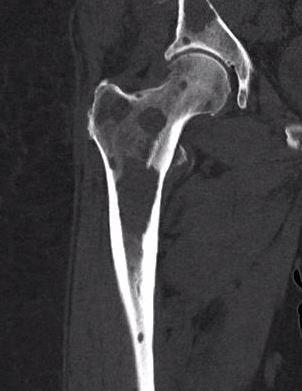

X-ray

1. Punched out lytic lesions

- axial and appendical skeleton

- widely disseminated

- soap bubble appearance

- no sclerotic reaction

2. Diffuse osteopenia

- in 15% to 25% of patients, no discrete lysis occurs

- diffuse osteopenia and osteoporosis are the only skeletal manifestations

3. Vertebrae Plana

4. Pathological Fracture

5. Pepper pot skull

Skeletal survey

Xray

- skull / spine / humerus / femurs / pelvis / chest & ribs

- low sensitivity

- only detect lesions with > 30% cortical destruction

Low dose whole body CT

- detects lesions < 5 mm